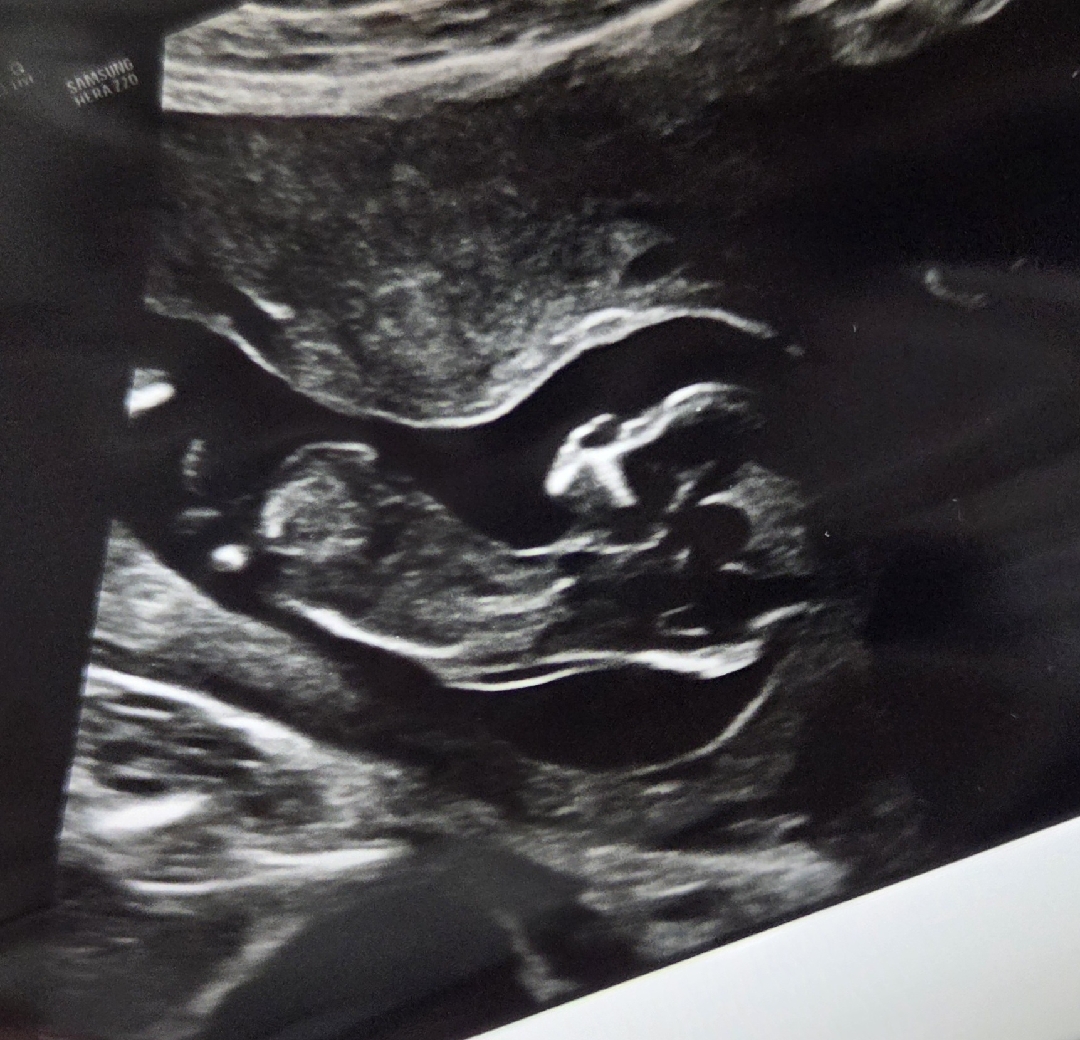

각도법 고수님들💖 한 번 봐주세요ㅎㅎ

12주 2일인데 어떻게 보이시나요?ㅎㅎ 전 막눈이라ㅠㅠ 도움 청해봅니다♡ ☆☆관리자님 질문방 댓글에 사진 안올라가요 점검 부탁드려용☆☆

생식기 돌기가 안 보이는 사진이예요

아~~! 어쩐지 어떻게 보는거지 했는데 안보여서 그랬군요ㅎㅎㅎ 감사합니다:)